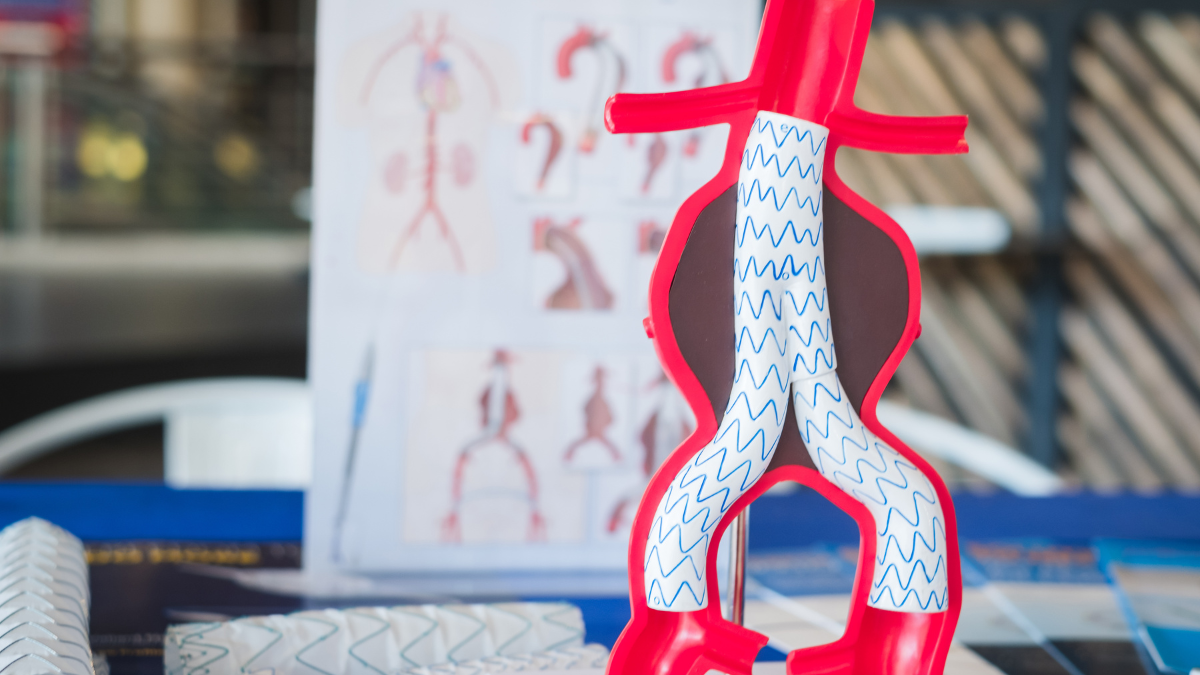

Endovascular Aneurysm Repair (EVAR) is a minimally invasive procedure that treats AAAs. Instead of making a large incision in the abdomen, which is common in traditional surgery, EVAR uses small incisions in the groin to access the aorta. A stent graft, a tube made of synthetic material and metal mesh, is then inserted through these incisions and placed at the site of the aneurysm. This stent graft reinforces the weakened section of the aorta and significantly reduces the risk of rupture.

The EVAR procedure typically lasts 2 to 3 hours and is performed in a controlled environment. You will receive anaesthesia to ensure your comfort, and the surgeon will make small incisions in the groin to access the femoral arteries. A thin wire will be guided through your arteries to the site of the aneurysm, followed by the catheter, which will deliver the stent graft.

The stent graft is positioned precisely at the aneurysm site and expanded, sealing off the aneurysm from the blood flow. Throughout the procedure, our surgical team will monitor your vitals and communicate with you to ensure your comfort and safety.